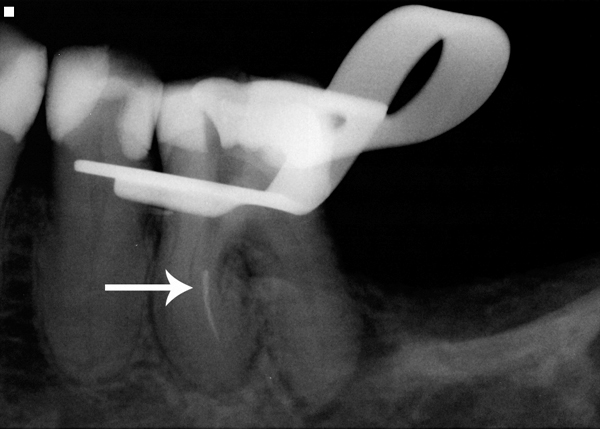

Fig 1. A separated rotary NiTi file can pose a risk of post-endodontic complications.

Figure 1

Rotary nickel-titanium (NiTi) files are commonly used instruments for performing endodontic procedures. However, while providing improved canal access, these types of flexible, mechanical files can be fragile and possibly break within the canal (Figure 1). In addition to posing an increased risk of post-endodontic complications, a broken file can cause both the clinician and patient added stress.

Even with the best preventive measures, endodontic rotary files can still separate within a canal (Figure 4). Although there are many file removal systems on the market today, the chance of successfully removing a broken file depends mainly on where it is located within a canal and the canal morphology. A study by Shen showed that the removal of a fractured NiTi instrument is more influenced by tooth anatomy, degree of root canal curvature, and fragment location than a specific technique.10 A study by Souter concluded that the limited success of file removal, increased risk of perforation, and reduced root strength suggest that file removal beyond the curved portion of the root should not be routinely attempted.11